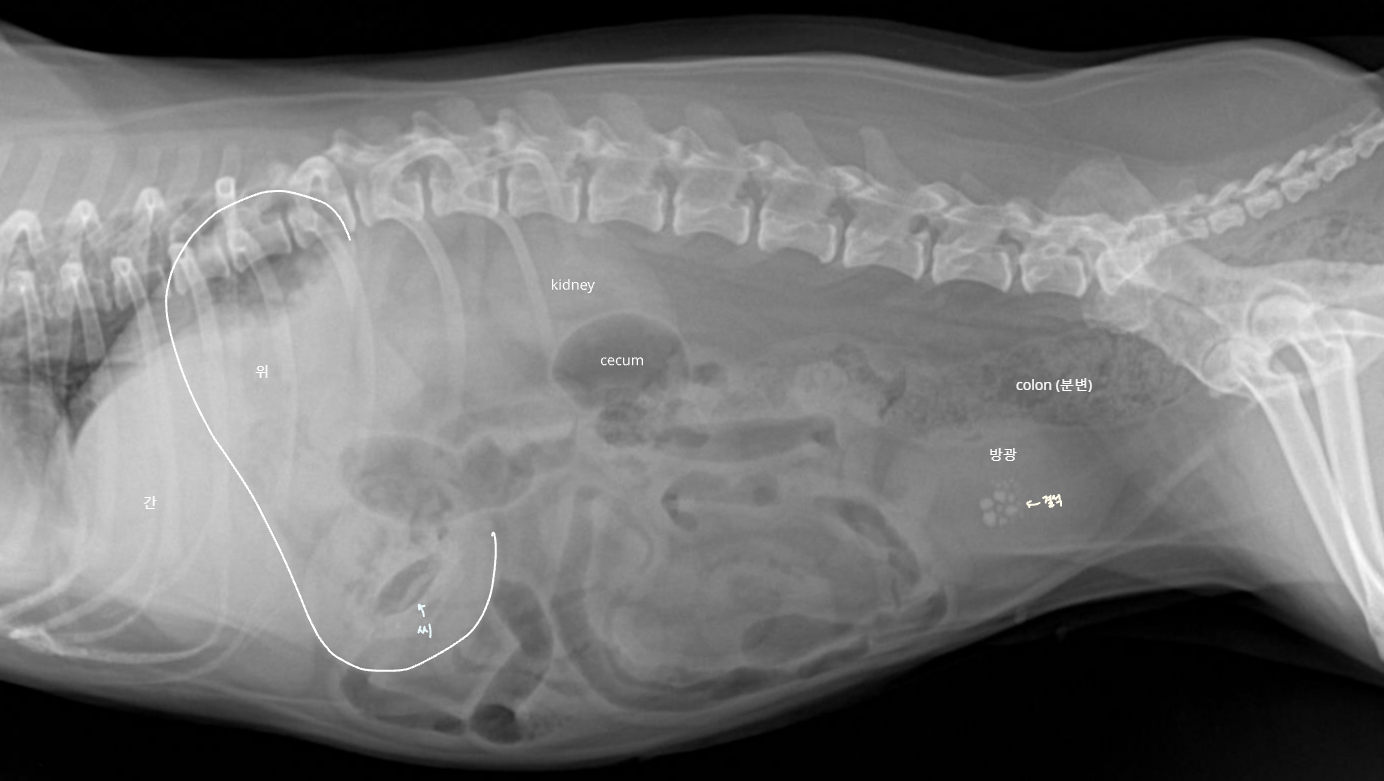

Anatomy (๋ณต๊ฐ ์ฅ๊ธฐ์ ์์น)

| Lateral |

|---|

| - stomach : ๊ฐ ์๋ gas๊ฐ ์ฐจ ์๋ ๊ตฌ์กฐ (์ฐจ ์๋ ๊ฑด ๋ค๋ฅผ ์ ์์) - duodenum : ์์ ๊ฐ์ด๋ฐ์์ ๋ป์ด๋๊ฐ - cecum : ์ฐ์ธก, ์ฌ์ฅ ์ฃผ๋ณ, gas๊ฐ ์ฐจ ์๋ ์ํ์ฑ ๊ตฌ์กฐ. (์์ ๋ฑ์ผ๋ก ์์น ๋ณํ ์ ์์) |